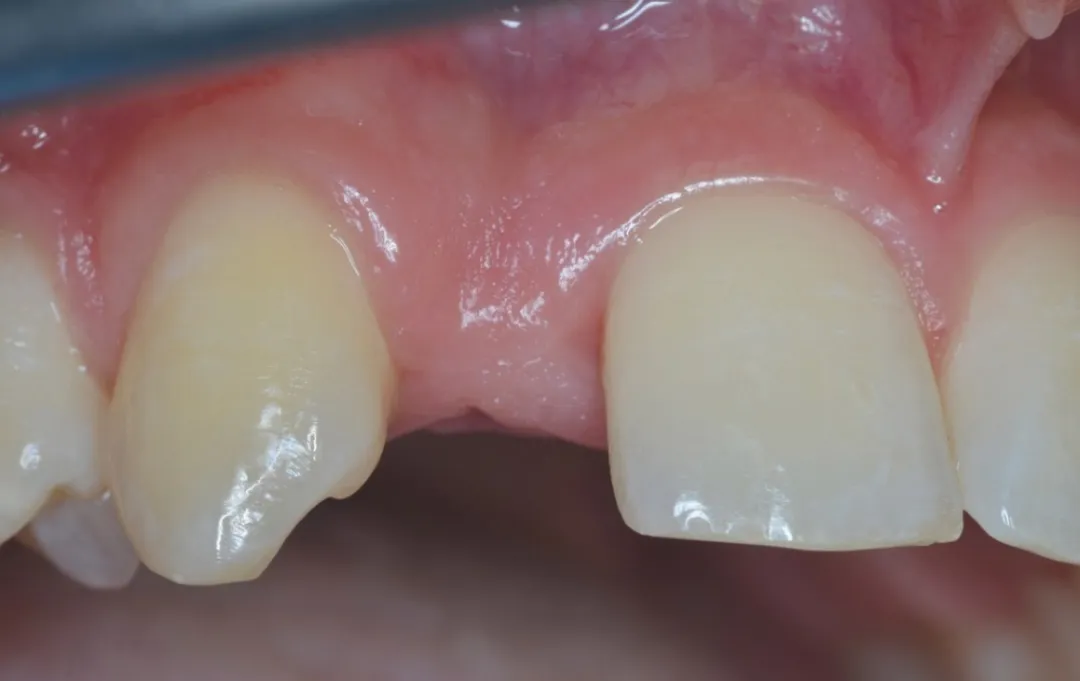

图 48 :术后 1 年口内情况。